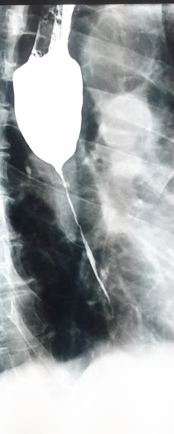

Postoperative stricture development at the esophagogastric anastomosis (Courtesy Dr. V. Penopoulos)